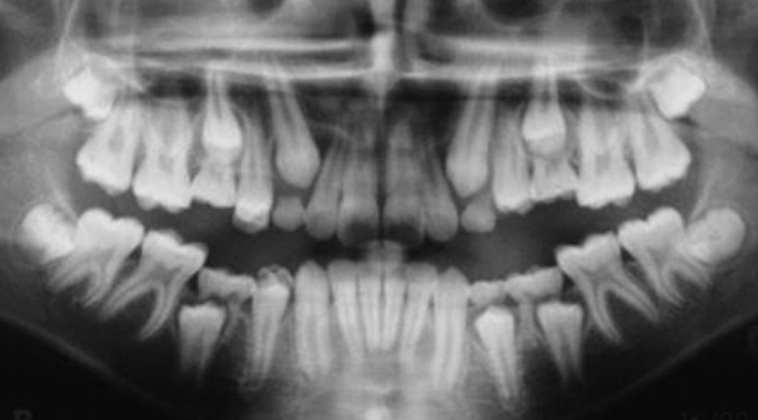

Permanent lower incisors present? Yes, so definitely 6-7

Permanent upper Incisors not erupted yet. Therefore not 7-8 y.o.

Conclusion = 6 y.o